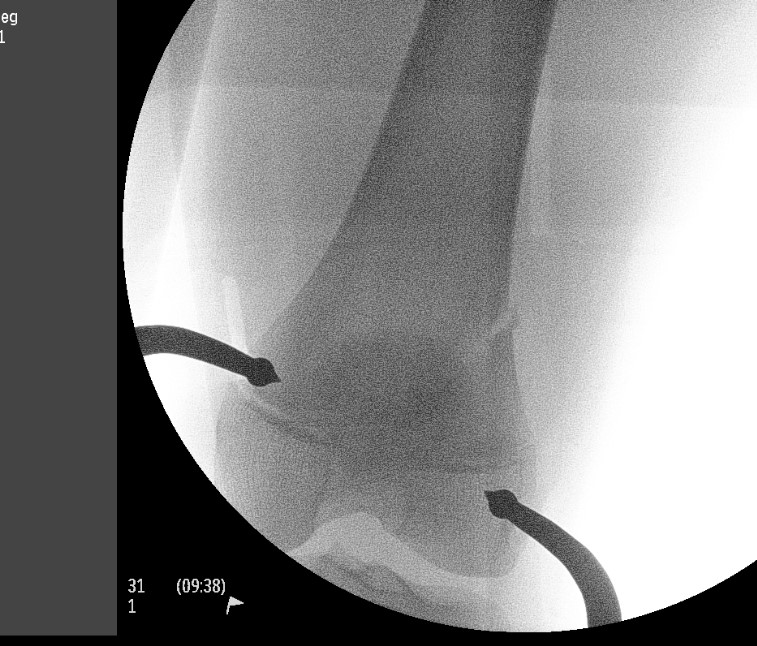

Displaced

MUA +/- ORIF

Low threshold to ORIF to maintain position

MUA

Block to reduction

- often medial sided periosteum

- may need small medial subvastus / anteromedial approach